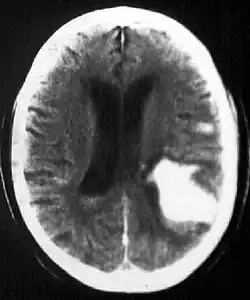

Other causes of intraparenchymal hemorrhage include hemorrhagic transformation of infarction which is usually in a classic vascular distribution and is seen in approximately 24 to 48 hours following the ischemic event. This hemorrhage rarely extends into the ventricular system.

Diagnosis

Computed tomography (CT scan): A CT scan may be normal if it is done soon after the onset of symptoms. A CT scan is the best test to look for bleeding in or around your brain. In some hospitals, a perfusion CT scan may be done to see where the blood is flowing and not flowing in your brain.